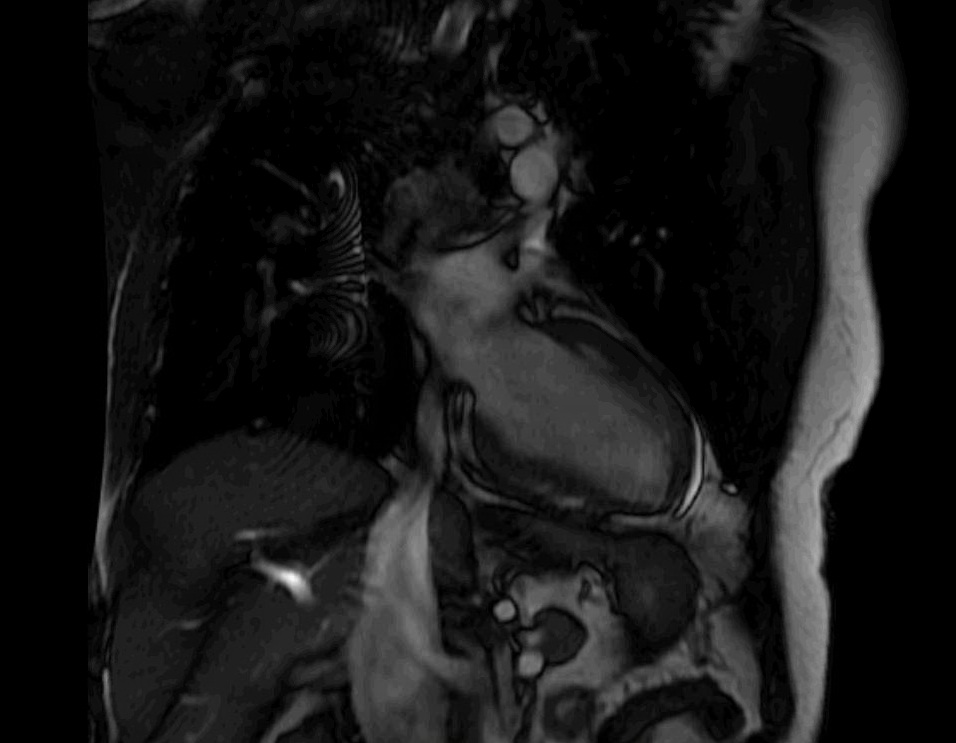

Case Presentation: A 45 year old African American male with sarcoidosis (2009 lung biopsy) was brought by EMS after an out of hospital ventricular fibrillation cardiac arrest. With ACLS, ROSC was attained after 20minutes. He had no family history of sudden death or heart disease. He did not engage in any toxic habits. Exam showed tachycardia but regular rhythm without additional heart sounds or murmurs, rhonchorous breath sounds, and subcutaneous nodules along his lower extremities. Labs were notable for a peak troponin of 0.95ng/mL, but urine toxicology, alcohol level, electrolytes, BNP, TSH, HgA1c and lipid panel were normal. EKG showed sinus tachycardia but no ST segment changes. Cardiac catheterization showed non-obstructive coronary artery disease. Echocardiogram (TTE) revealed a left ventricular ejection fraction (LVEF) of 35%. Cardiac MRI became indicated. It showed transmural late gadolinium enhancement in mid to apical anteroseptal, inferolateral and lateral walls, as well as subendocardial enhancement in the basal anterolateral walls. The patient was initiated on prednisone 40mg daily and received an implantable cardioverter-defibrillator (ICD).